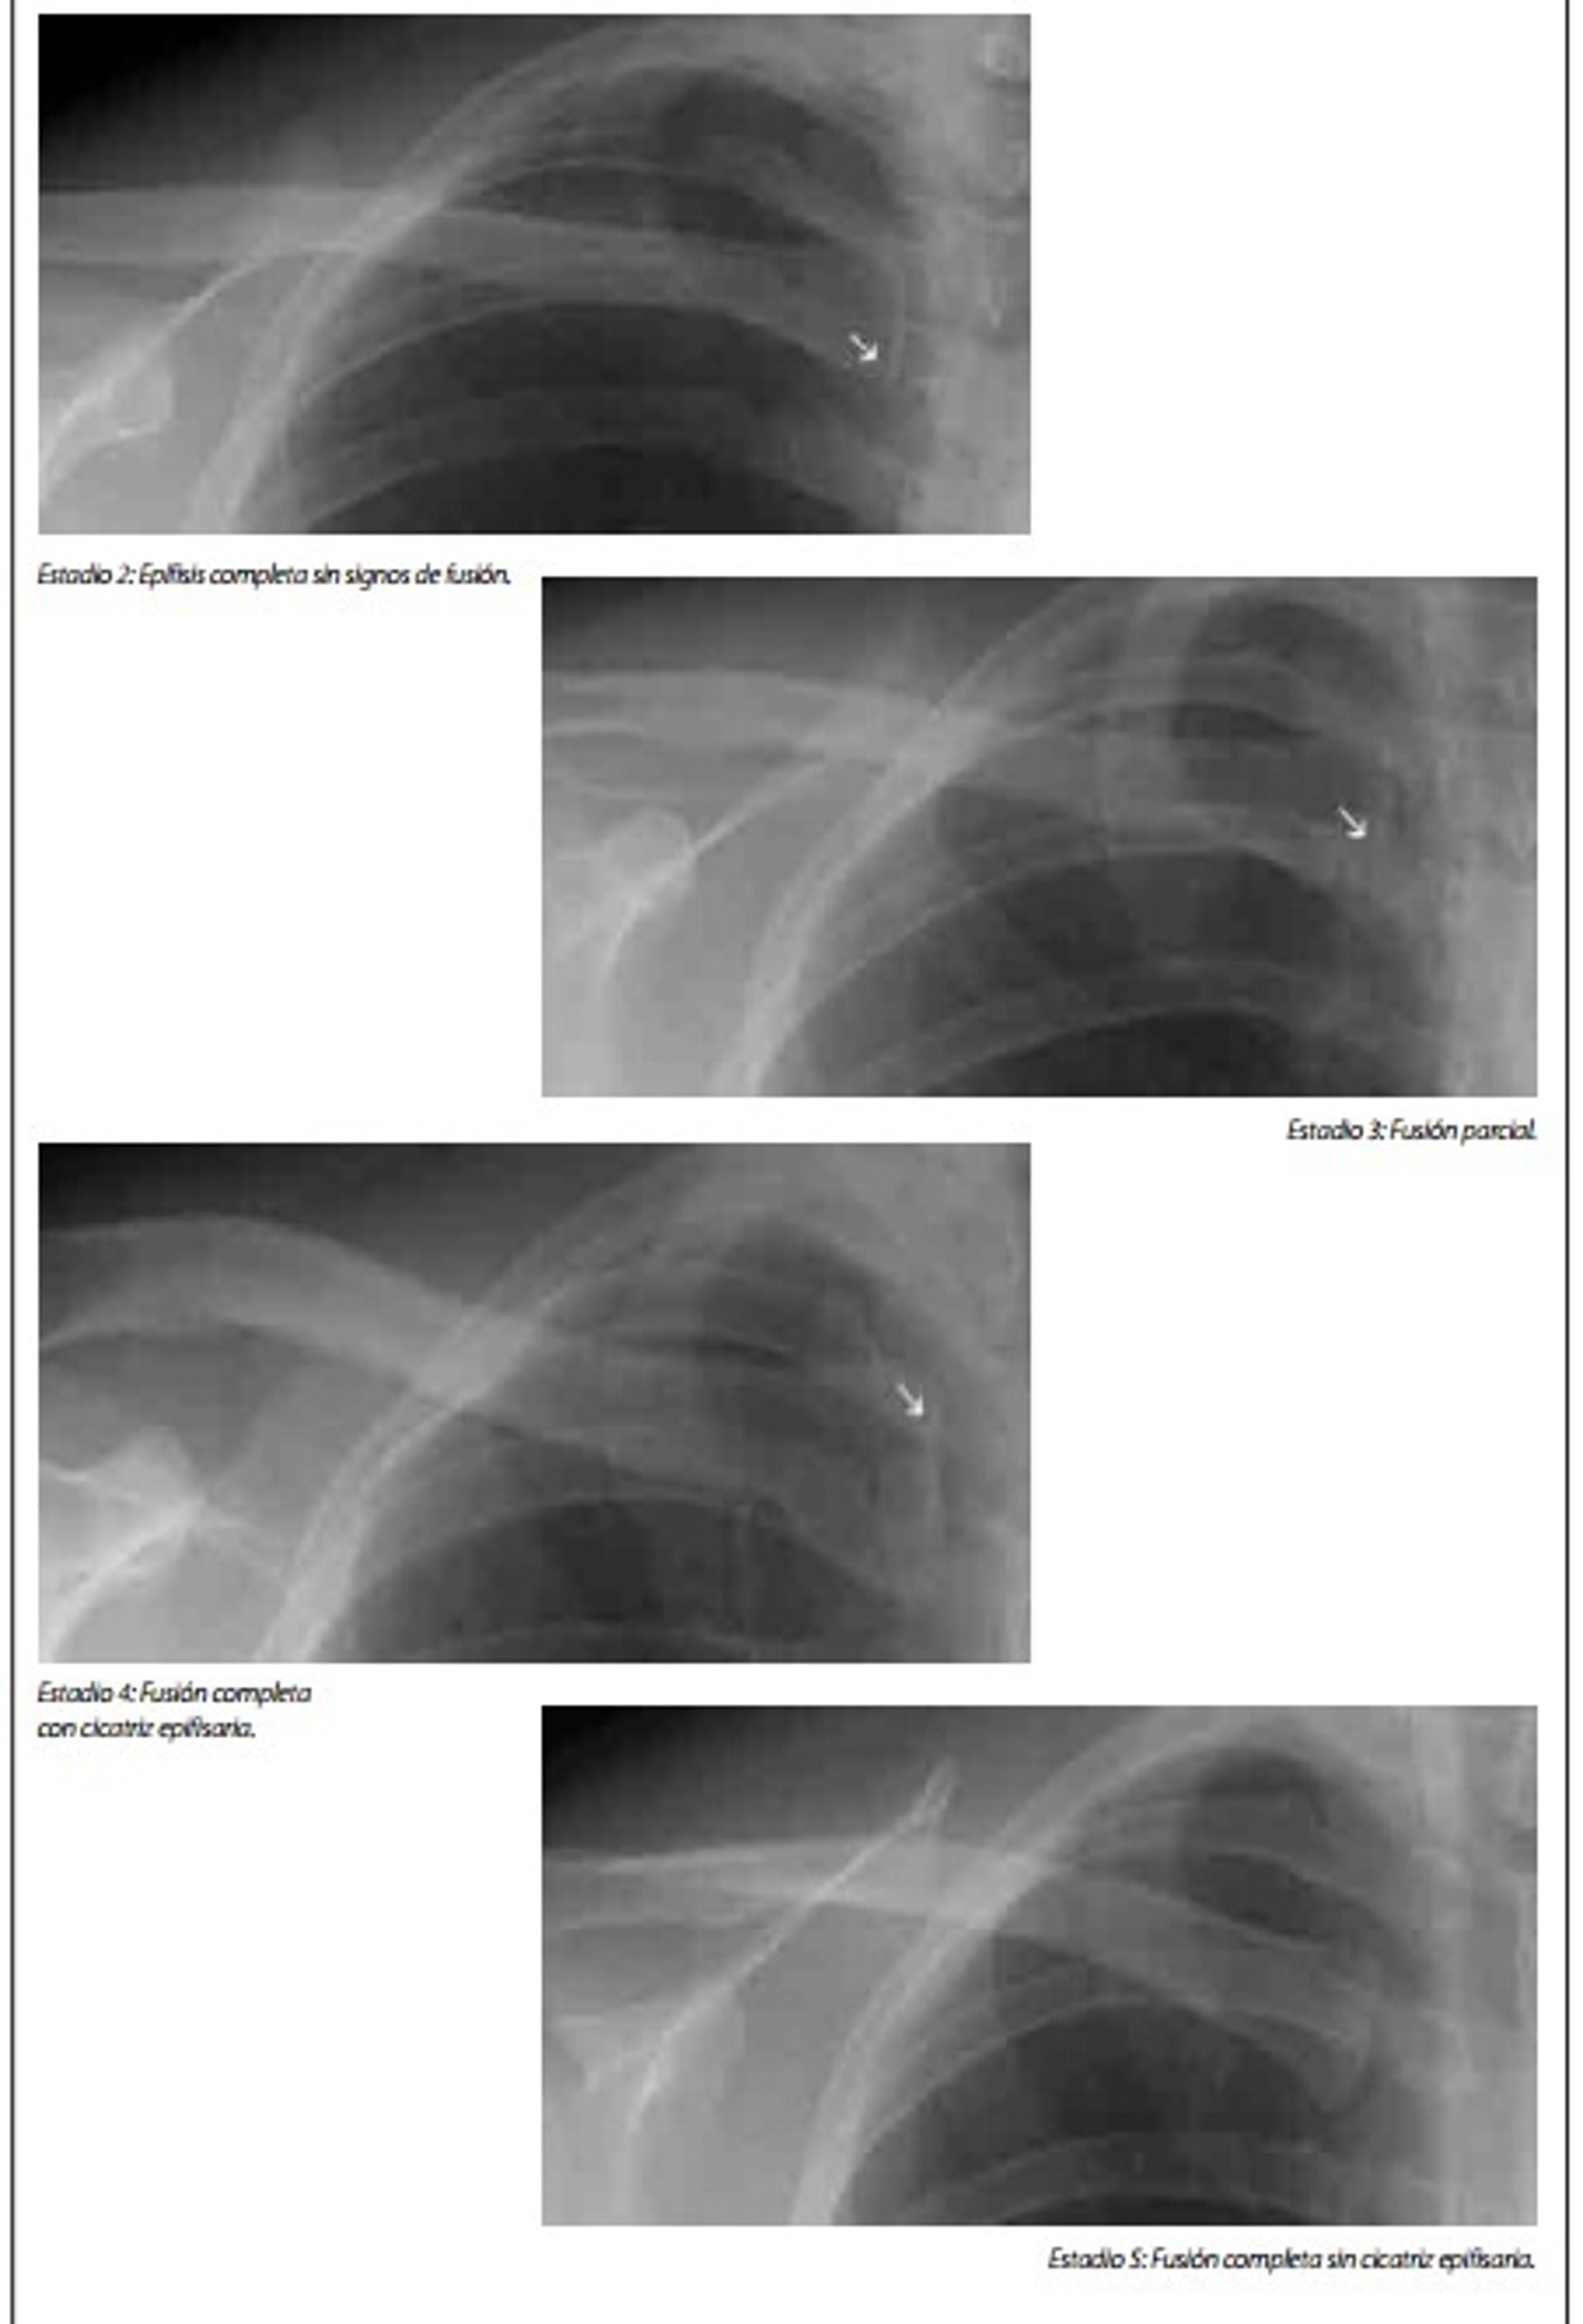

Lo explica a Europa Press la presidenta de Fundación Raíces, Lourdes Reyzábal, para denunciar "lo injusto" de un sistema en que "la palabra del Fiscal" y unas pruebas médicas que tienen un margen de error superior a dos años y cuya validez ha sido cuestionada entre otros por el Defensor del Pueblo, se imponen "por encima del interés superior del menor" cuando se trata de niños extranjeros que están solos en España.